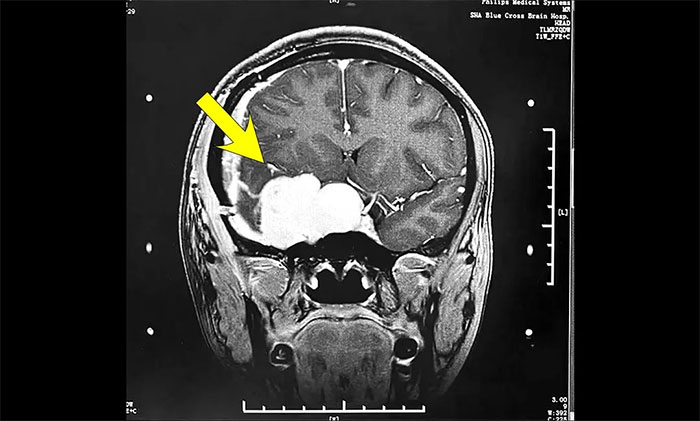

今年初医院收治了一位女性患者。该患者因突发视力模糊,头晕无法独立行走,在外院检查发现脑部右侧鞍旁肿块,手术病理诊断为海绵状血管瘤。

▲ 入院时MRI检查影像

肿瘤科(放疗)头部伽玛刀组陈琦主任完善检查并开展多学科评估讨论,其右侧鞍旁海绵状血管瘤与视神经等重要结构相邻,若不及时干预治疗,可因占位压迫进一步加重神经功能障碍,甚至导致失明。而该部位病灶的手术治疗难度高、风险大,术中可能对患者神经功能造成严重损害,应考虑采用创伤较小的伽玛刀治疗。